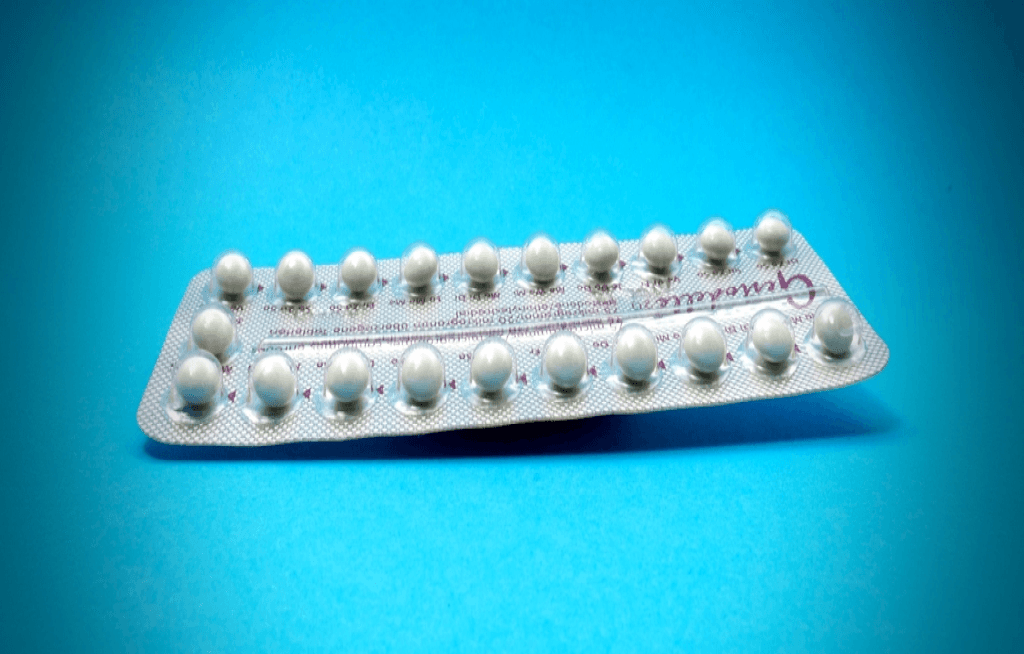

En la pantalla de una computadora, la foto borrosa de una bandera comienza a enfocarse. Surgen arrugas en su superficie, pliegues que ondean en un viento fantasmal. Al acercar la imagen de nuevo, empiezan a aparecer hilos. De nuevo, y hay un indicio de deshilachado en el borde. En este juego de manos digital, no […]